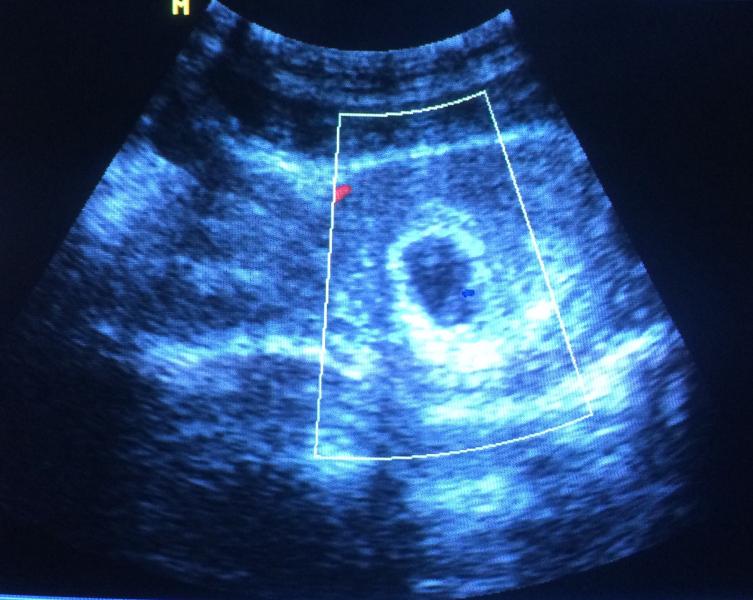

15 января. Первое Узи 😍 там такая кроха. 6 недель и 4 дня. Все в норме, правда есть небольшой тонус. Самочувствие заметно лучше. Рвоты сильной нет, тошнота присутствует, но не так противно. Начала есть немного. Мне помогли смесь орешков с сухофруктами, отдельно кисленькая курага и детское питание (пюрешки, кашки). Даже уже появился голод 😄 а то аппетита не было совсем. Так что, вот. Наблюдаем дальше за происходящим 👌🏻